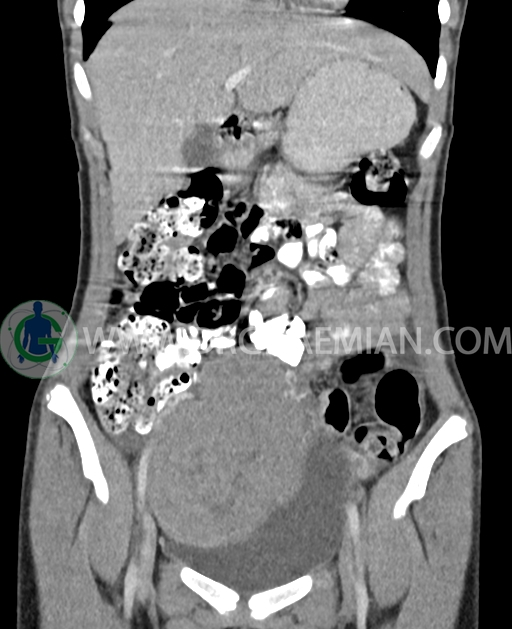

سی تی اسکن شکم و لگن از تشعشعات برای ایجاد تصاویر عرضی مقطعی از نایحه شکم و بین استخوان های لگن استفاده می کند. در این کیس تومور سلول زایا به ابعاد mm 125 x 112 x 80 دیده می شود.

در سی تی اسکن اسپیرال شکم و لگن با کنتراست خوراکی و وریدی (مولتی دیدکتور 16 با مقاطع ظریف و بازسازی های ساژیتال و کرونال) :

توده هیپردنس لوبوله بزرگ به ابعاد 125x112x80mm حاوی نواحی سیستیک داخلی و enhancement قابل توجه پریفرال همراه با آسیت متوسط در فضای شکم و لگن با احتمال بیشتر با منشا از تخمدان راست، درون لگن دیده می شود که در درجه اول مطرح کننده germ cell tumor می باشد .